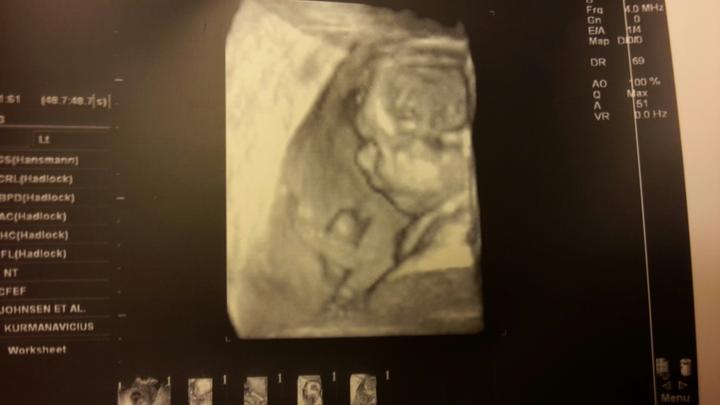

Tak dneska 3D ultrazvuk a 100% kluk 🙂

(3 fotky)